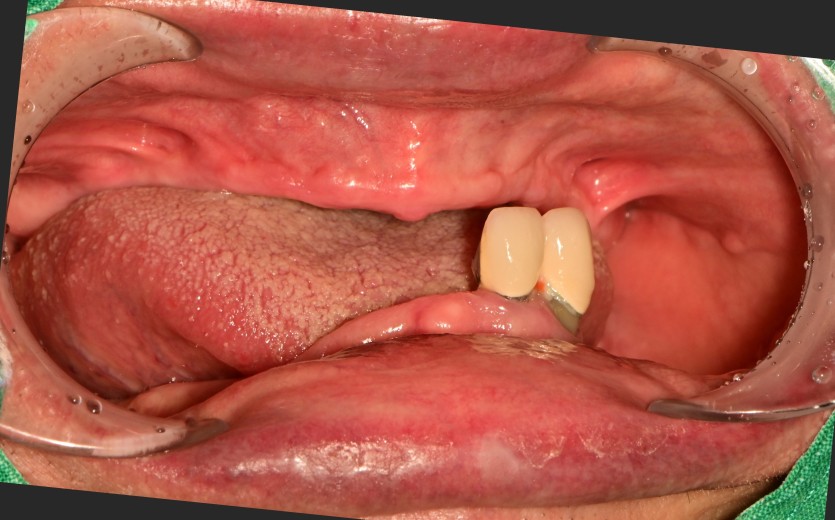

전체 임플란트 증례입니다.

18개의 임플란트로 완성하였습니다.